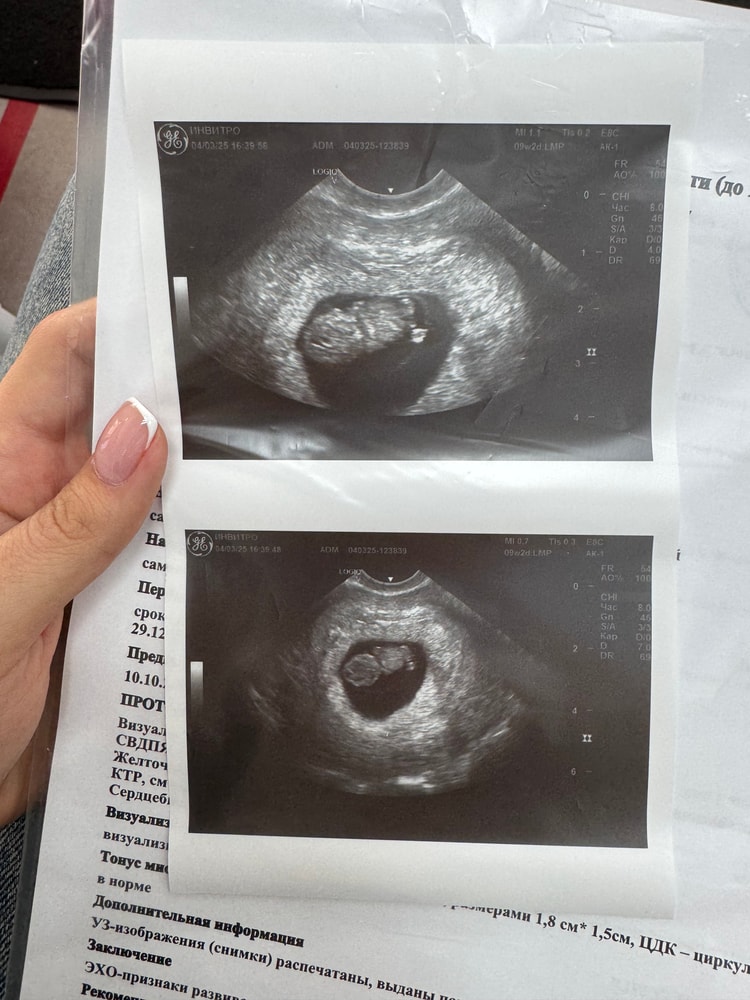

Девочки, привет, кто знающий и разбирается в снимках узи раннего срока, посмотрите пожалуйста, вообще ничего не понимаю 😅 Где голова, где что? 😂 Ручек, ножек вообще ещё не видно получается? Смотрела снимки других девочек на этом сроке, уже хоть как-то можно человека высмотреть, а у меня фасоль 🤦♀️ Это нормально, что он так выглядит?..( Врач смотрел пол минуты и ничего не объяснил, поэтому обращаюсь к Вам, всегда здесь подскажут и помогут ❤️

Срок по узи ставят 8 нед. Ктр 17,8 мм

Мне кажется, что это вид сзади, спинка

Отправила вам в личку свой 3D снимок на точно таком же сроке 🤗 у вас правда просто со спины)

Их просто не видно, возможно, вообще на снимке спинка. С таким КТР ручки и ножки уже точно формируются.

Да мне кажется, что это вид сзади) Ходила в 8.4, мне два снимка дали, один со спинки, тоже ничего не понятно, и один нормальный, там и голову и жопку видно, креветочка такая. Видимо просто узист не стал заморачиваться со снимками. Растите 🌸

Да, похоже что просто сзади сфотографировали малыша) врачи на таких сроках особо не стараются в фото😃

По мне так головка внизу, а вверху виднеется часть ножки